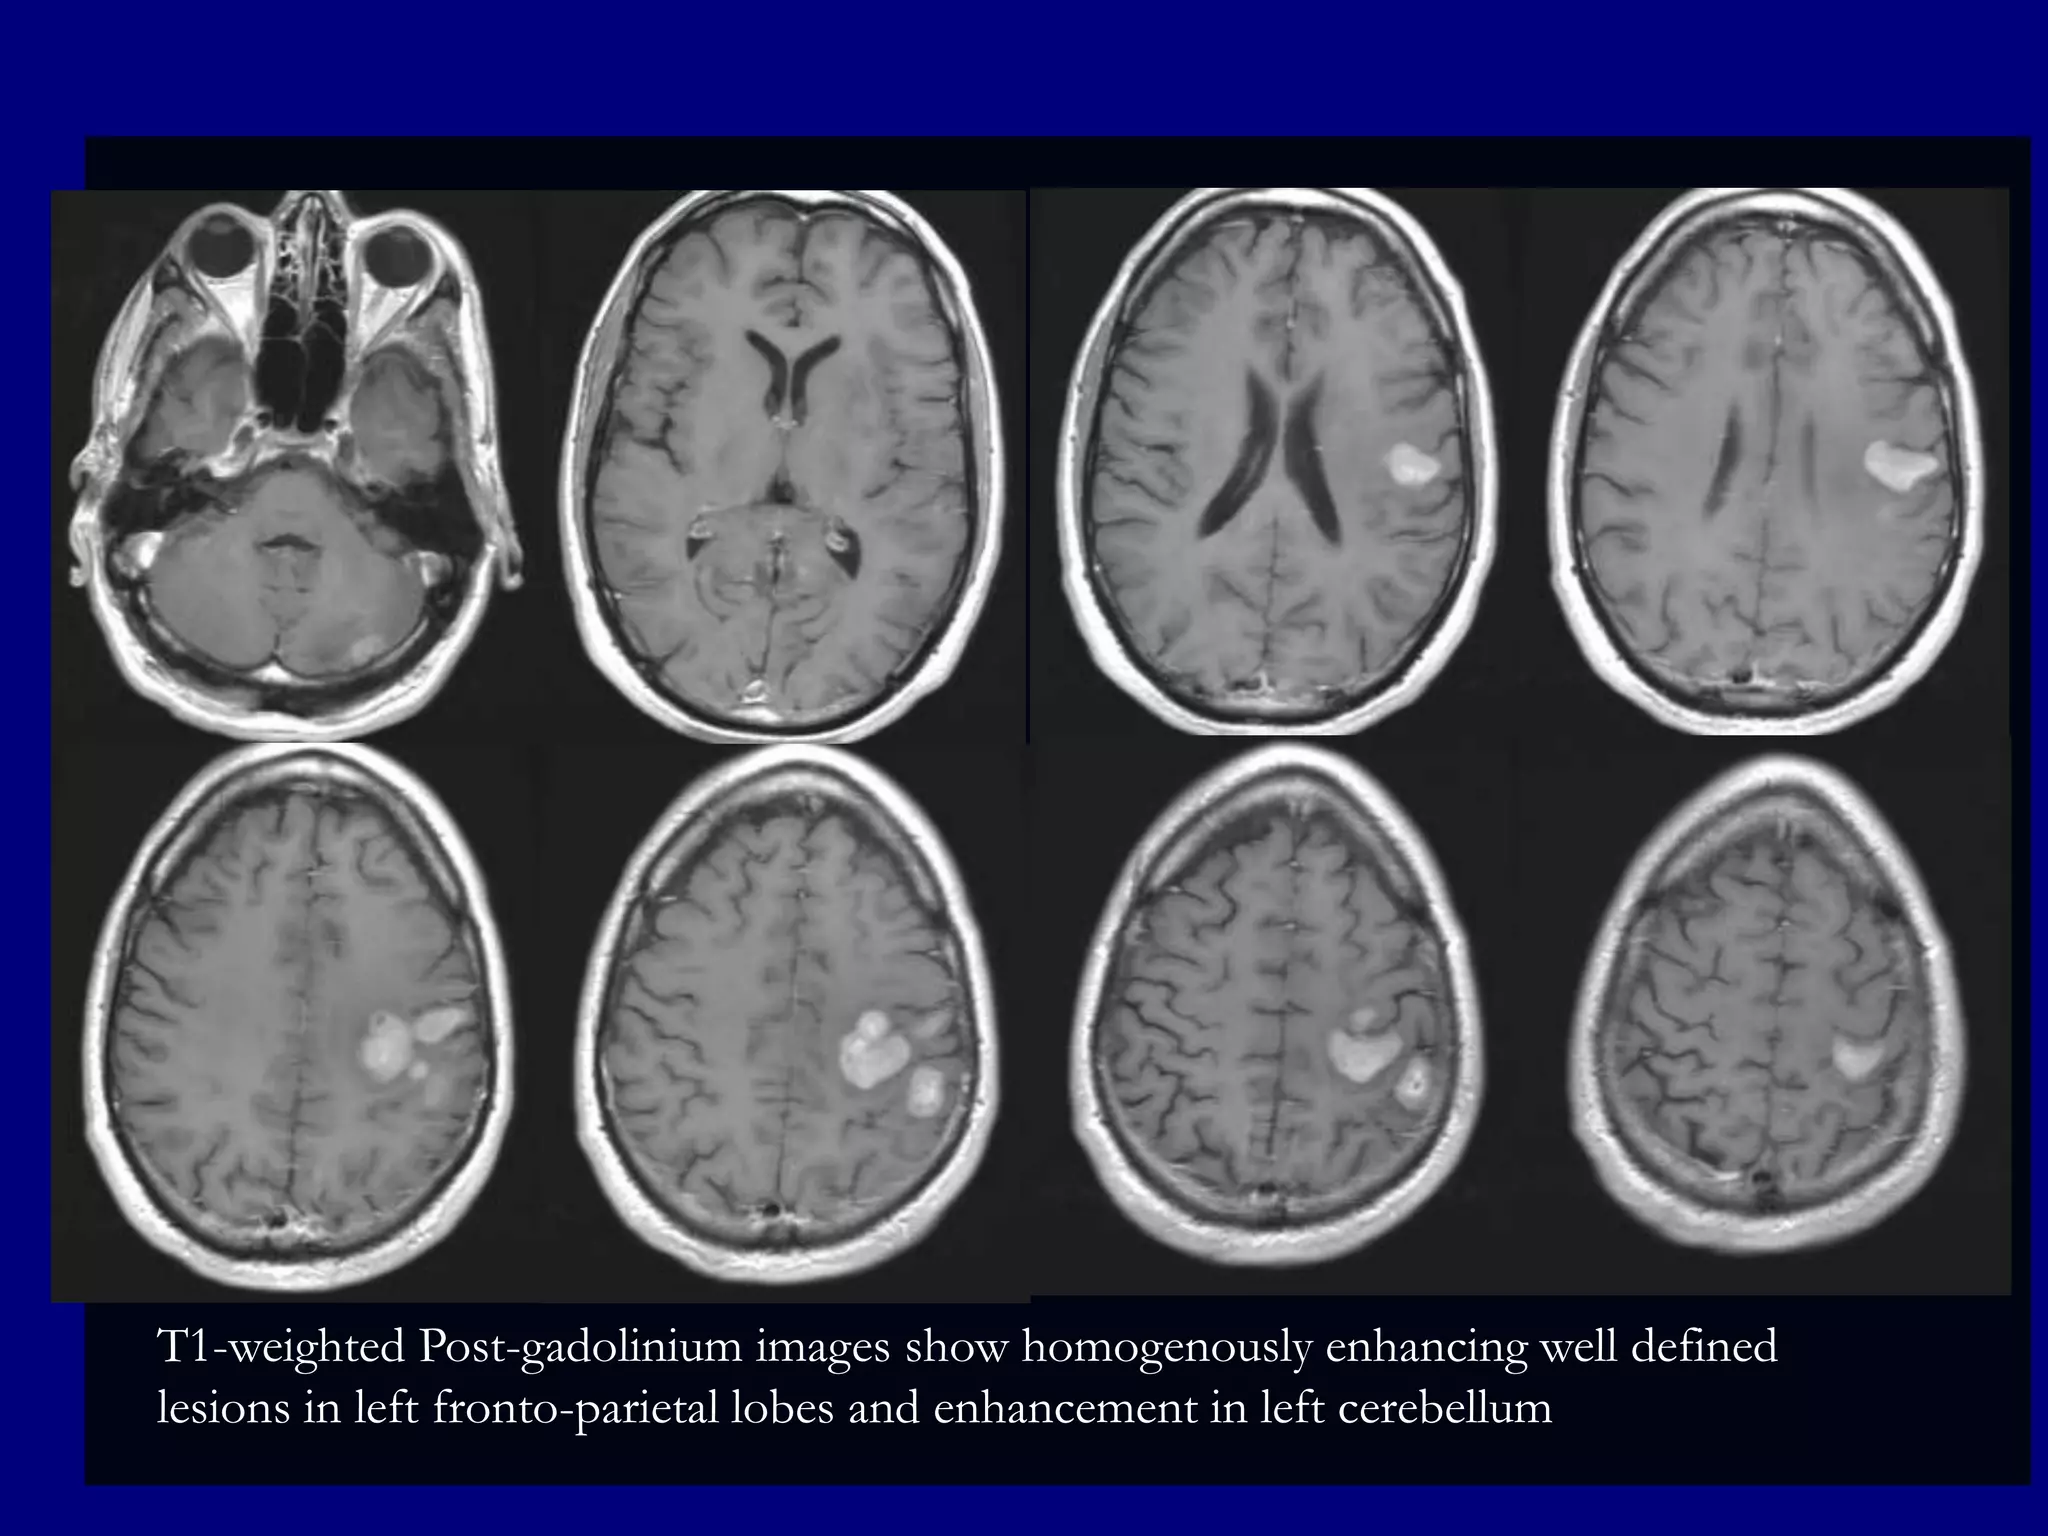

T1-weighted Post-gadolinium images show homogenously enhancing well defined

lesions in left fronto-parietal lobes and enhancement in left cerebellum